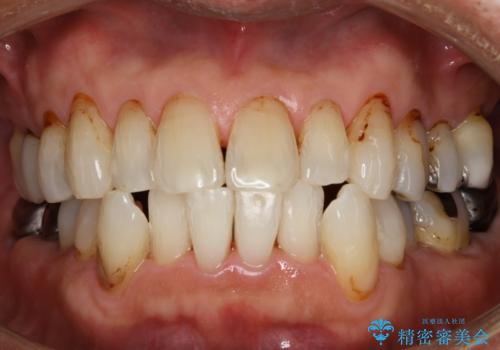

[ 虫歯・歯周病・インプラント ] 全顎補綴治療

![[ 虫歯・歯周病・インプラント ] 全顎補綴治療の症例 治療後](https://seimitsushinbi.jp/wp/wp-content/uploads/2025/08/382c499e19e22dcf6f8af5ed1cea2d03-500x350.jpg?v=1754470273)